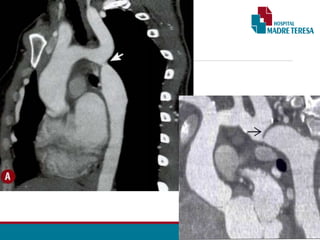

ANGIOTOMOGRAFIA DA AORTA TOTAL 11/06:

• Achados pós-operatórios de correção de coarctação de aorta (dado clínico), havendo próteses

valvar aórtica e na aorta ascendente, patentes. Há ainda endoprótese aórtica, também

pérvia, com ancoragem proximal na região da emergência da artéria carótida esquerda,

estendendo-se até o terço médio torácico descendente. Não há evidências de endoleak.

• Fios de esternorrafia bem posicionados.

• Pequena coleção hipoatenuante alongada retrosternal, com focos gasosos em permeio,

apresentando volume grosseiramente calculado em 23 cm³.

•Associa-se pequeno / moderado pneumomediastino, além de pequeno pneumoperitônio.

•Pequeno derrame pericárdico.

•Pequeno derrame pleural bilateral hipoatenuante.

•As demais porções da aorta torácica descendente apresenta diâmetro usual.

•Houve redução da dilatação de artérias intercostais e torácicas internas, na comparação com

estudo tomográfico prévio do dia 28/05/2019 (exame pré-operatório).

•Artérias ilíacas comuns, internas e externas estão patentes.

Obs.: Como achados de exame não direcionado, verificamos: Pequena ascite.